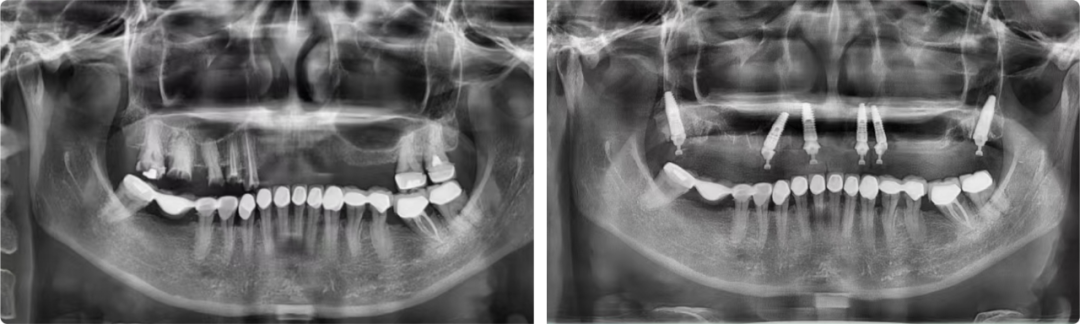

做完CBCT檢查,張潔發(fā)現(xiàn)患者的情況非常棘手:牙槽骨骨量不足、骨質疏松,能選擇的種植點位非常有限且靠近上頜竇,種植體容易穿透,造成種植失敗。張潔為患者精心制訂了All-On-6半口即刻負重穿翼種植手術方案,這個方案難度很高,但效果最為理想。

患者術前術后全景片

事實證明,手術難度超出預期:拔第一顆牙就發(fā)現(xiàn)有粘連,牙槽骨存在慢性炎癥,而這個點位是準備做穿翼板種植的。“這種情況真是雪上加霜!每一顆我都做得非常謹慎,需要把手感發(fā)揮到極致,但凡有一顆種不上,手術到此結束,整個治療方案就會失敗!”術中,張潔不斷提醒自己再細一點,手感再好一點。

這臺手術歷時三個半小時,比平時多花了一倍多時間,所幸的是六顆種植體全部成功負重。術后,患者順利戴冠,咬合良好。